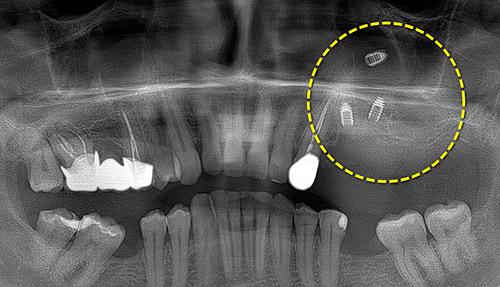

Создание условий для имплантации

Если костная ткань челюсти значительно атрофирована, установка имплантов и протезов становится невозможной. Все исправляет хирургическая стоматология:

• посредством аугментации костной ткани;

• посредством синус-лифтинга.